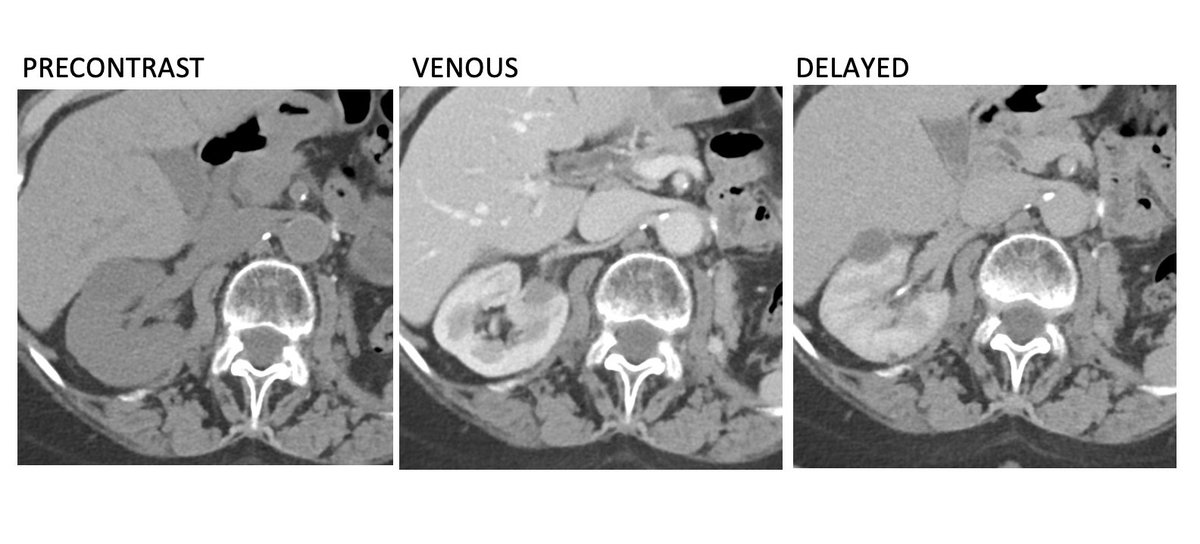

1/ History of left kidney clear cell renal cell carcinoma status post nephrectomy. What is your recommendation based on this surveillance CT scan?

2/ The majority of renal cell carcinomas are clear cell variant, the most vascular & malignant variant. Arterial phase imaging (lacking from above study) is critical to identify recurrent disease. Vascular metastases become invisible on venous & delayed phases. (Answer is D)

7/ Bottom line...reduction of unnecessary radiation exposure is our priority, but don't eliminate the arterial phase in patients with a history of clear cell RCC or you will miss early recurrence and metastatic disease.